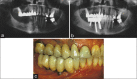

Panoramic radiographs before and after implant treatment in the right edentulous mandible (a and b); clinical view after treatment (c)

Figure 7